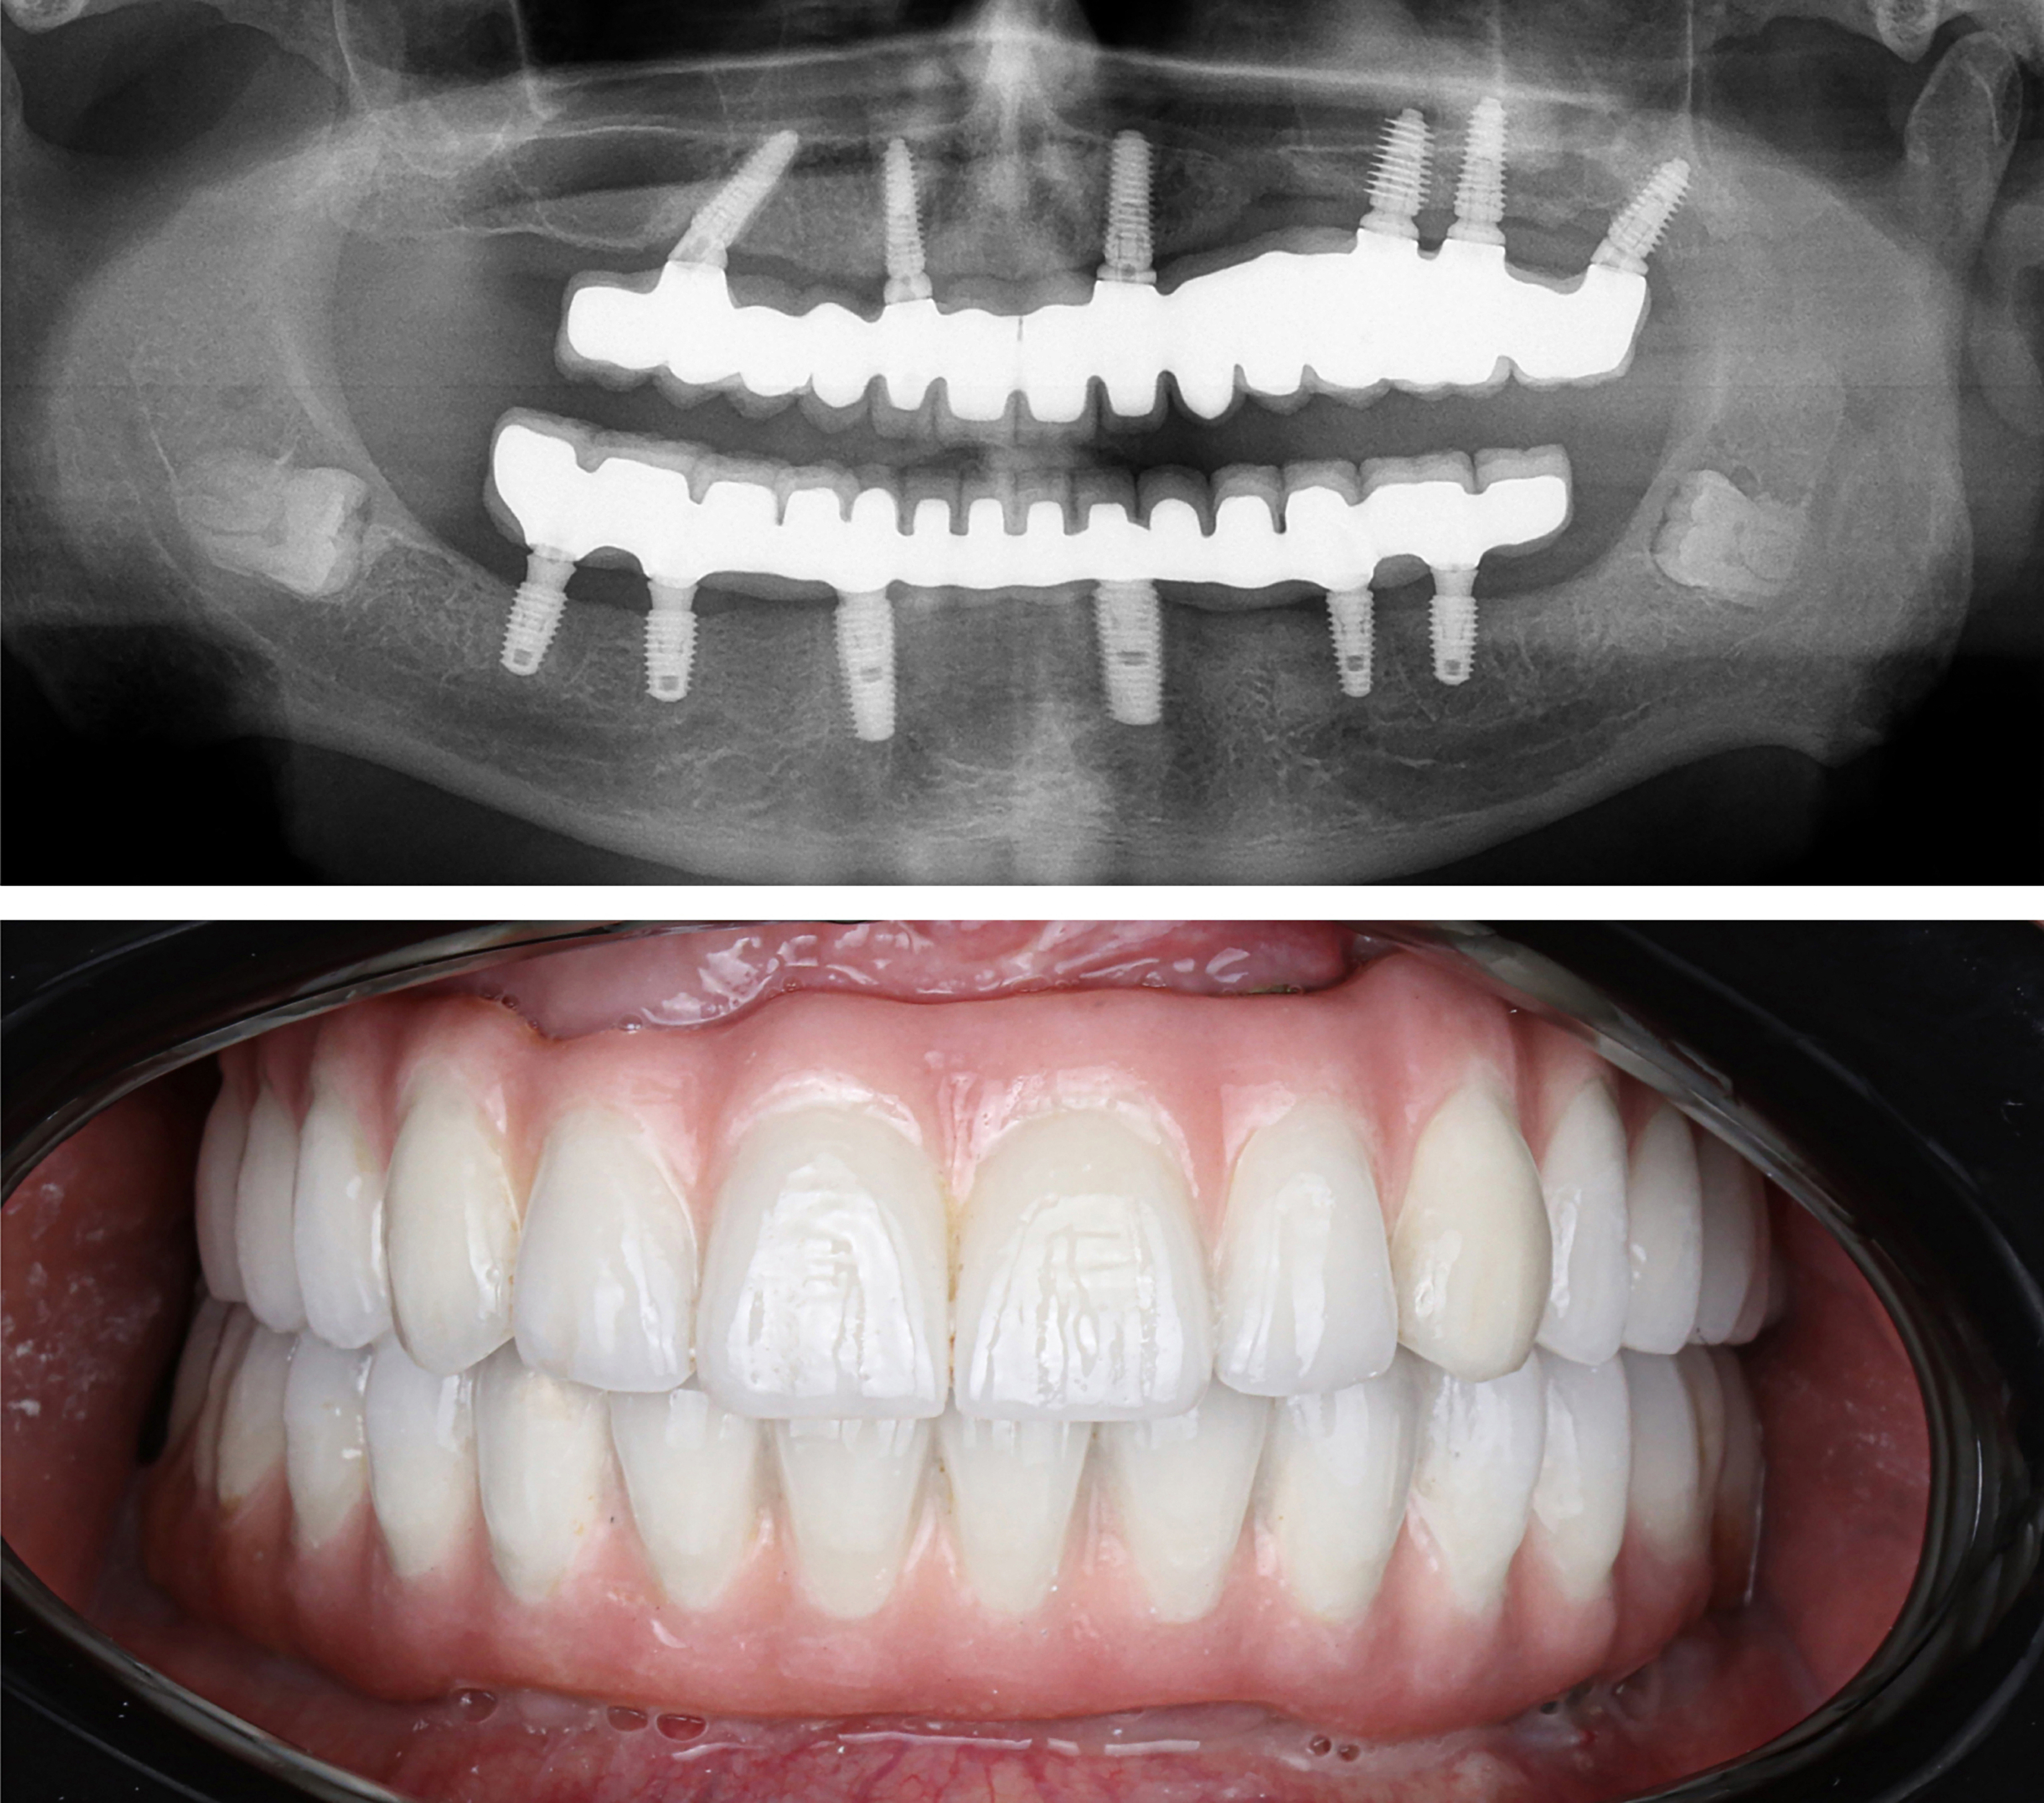

Example transformations achievable with dental implants

What are dental implants?

Learn how millions of Americans are replacing their teeth for life!

Patients no longer have to deal with low-quality temporary solutions like dentures, bridges, or partials. Dental implants are the new leading standard in tooth replacement options. They act and feel just like real teeth with an average lifespan of 20+ years.

So, how do they work?

Every single dental implant consists of three parts - the implant, the abutment, & the crown. The implant is made of medical grade titanium. This part is surgically placed into the patient’s jaw bone and left to heal for 4-6 months afterwards.

This implant piece acts as the foundation for the rest of the tooth. Once the bone around the site has healed, the abutment and crown are placed on top of the implant. The end result is a beautiful, natural-looking new tooth!

Few people will ever be able to tell the difference between your implants and your real teeth.